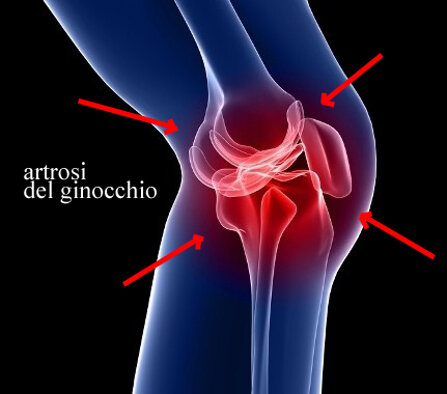

L'artrosi del ginocchio, come tutti immaginiamo, è una malattia molto frequente nella nostra società e, in considerazione della crescente aspettativa di vita, in continuo aumento, con una frequenza che varia dal 27% al 44% (popolazione sopra gli ottant’anni).

I sintomi dell’artrosi al ginocchio sono molto variegati e ogni soggetto coinvolto ne ha una rappresentazione del tutto personale.

Molto spesso il dolore è evidenziato nello scendere e salire le scale e può essere associato alla sensazione sia uditiva che tattile di scricchiolii e sfregamenti .

La sensazione fastidiosa, localizzata a tutta la zona femoro-tibiale, compare quando si cammina anche per poche decine di metri e si accentua particolarmente nei movimenti e circostanze che prevedono un eccessivo carico (fare le scale, portare le borse della spesa).